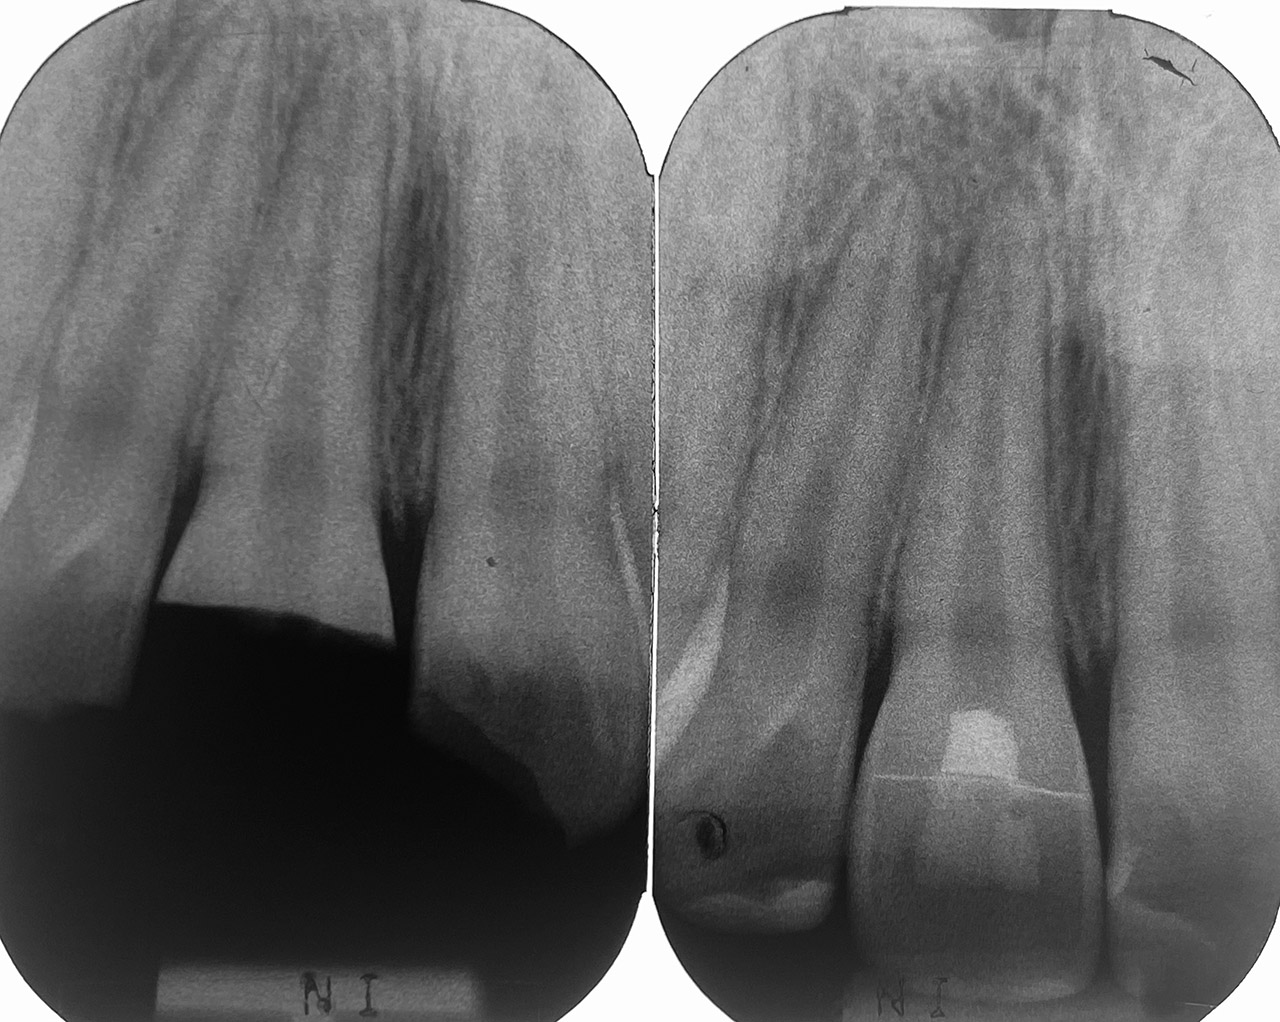

Traumatologie und Endodontie:

Nach Unfall/Sturz mittlerer Schneidezahn auf Gingivaniveau abgebrochen, Pulpa weit eröffnet, beide Nachbarzähne ebenfalls frakturiert.

Erstversorgung: Pulpektomie der Kronenpulpa, MTA, provisorischer Verschluß mit rosa Glasionomerfüllung.

Wiederaufbau der Nachbarzähne mit mitgebrachten (plus 1 Stein) Zahnstücken mit Kunststoff ergänzt und adhäsiv verklebt.

2. Schritt nach Aushärtung von MTA: Entfernung der Kronenpulpa im Bruchstück zur Vermeidung von Verfärbung, Füllung mit Kunststoff.

Adhäsives zementieren des abgebrochenen Zahnstücks.